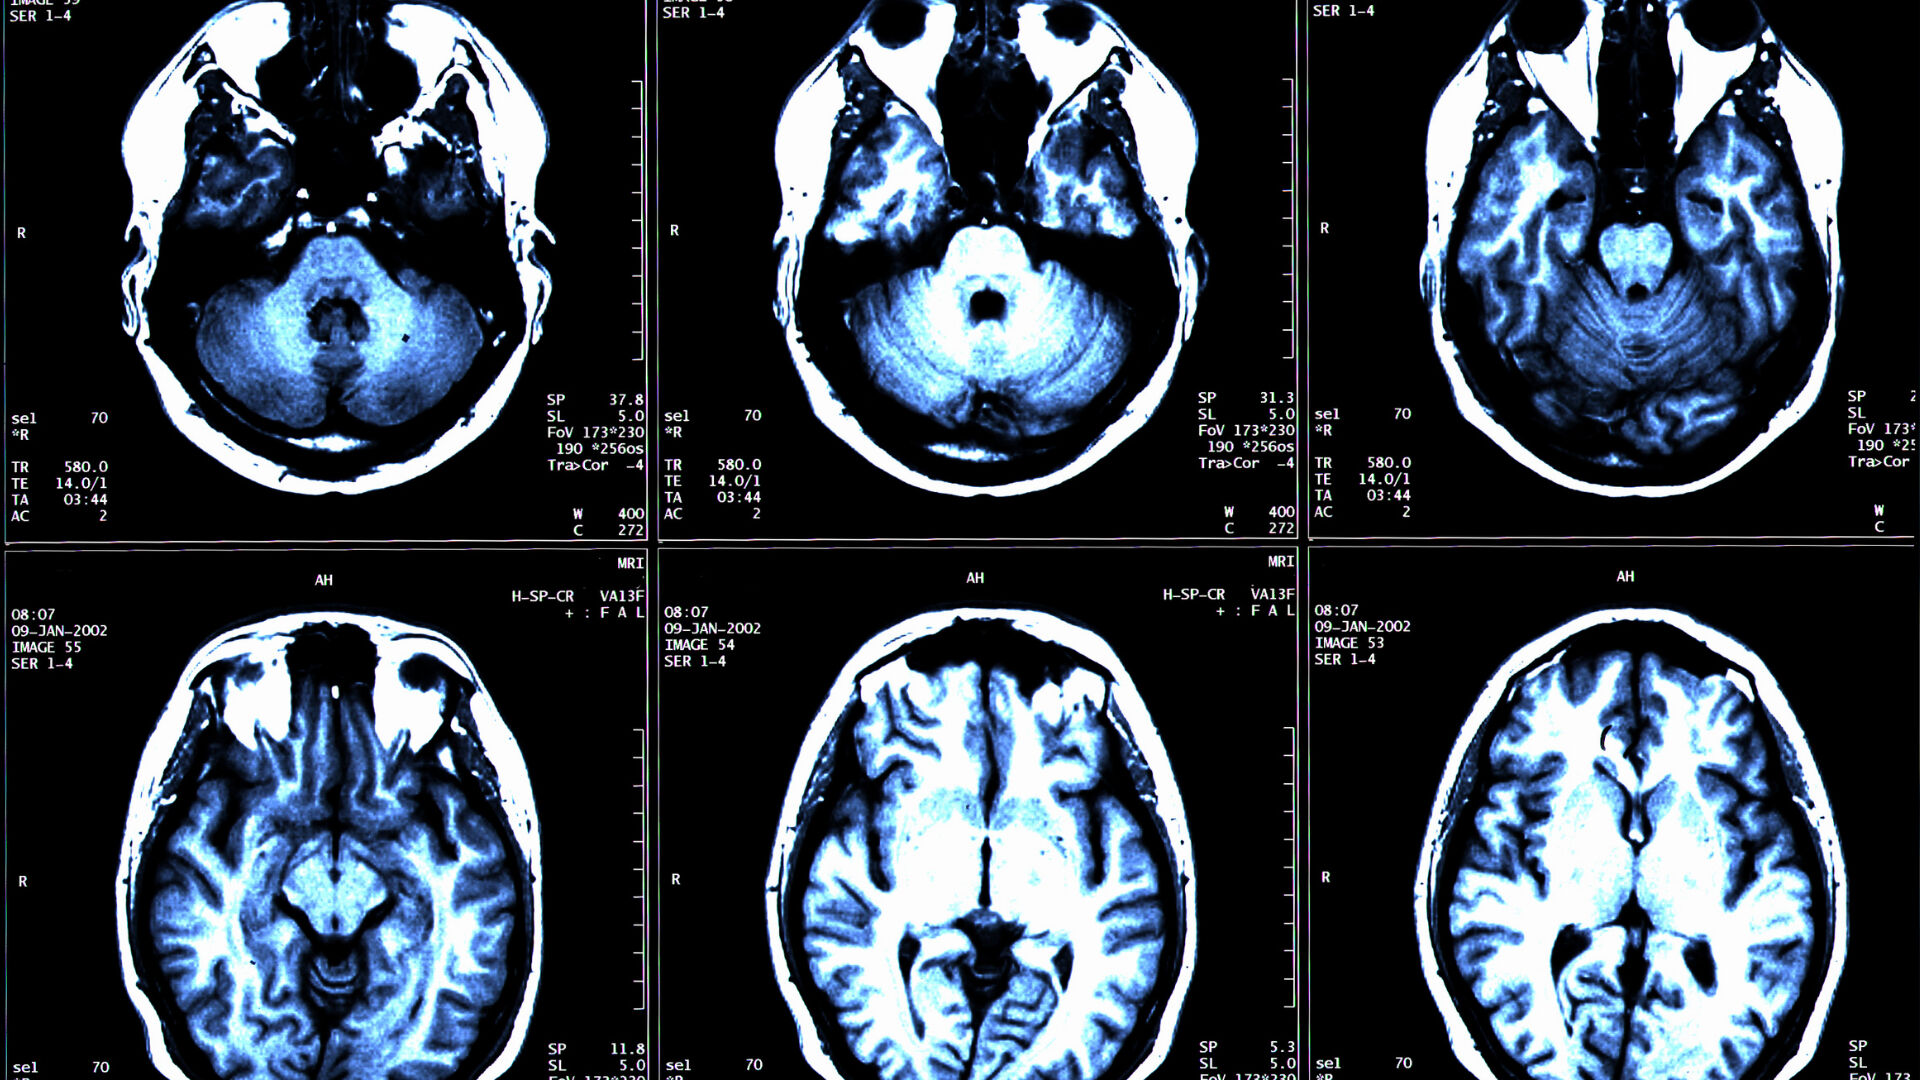

Disdiadokokinezi, beyincikteki bir sorunun göstergesi olarak kullanılıyor. Hareketle ilgili sağlık problemleri, beyin tümörlerinden sinirsel bozukluklara kadar birçok hastalığın belirtisi olarak kabul ediliyor.

Disdiadokokinezi; beyin tümörleri, multipl skleroz başta olmak üzere sinir sistemini etkileyen birçok hastalıkla ilişkilendiriliyor. İngiltere’de 40 yaş altı bireylerde en ölümcül kanser türü olarak bilinen beyin tümörleri, görme bozukluğu, baş ağrısı, konuşma sorunları, davranış bozuklukları ve kas güçsüzlüğü gibi birçok sorunu beraberinde getiriyor.